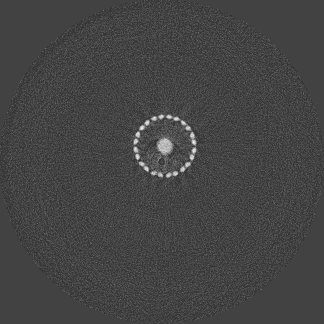

For the beam hardening study, we used Medipix All Resolution System (MARS) [12] containing a Medipix3RX ASIC with a 2 mm CdTe sensor bump bonded at 110 μ𝜇\mum in a single chip layout. All the acquisitions in this paper were carried out in CSM. The detector assembly is a module of the MARS camera which also contains a readout board, peltier cooling system and an integrated bias-voltage board. A negative bias voltage of -440 V was applied across the sensor during the acquisitions. The MARS scanner system comprises of MARS camera, a rotating internal gantry and an 80 kVp Source-Ray SB-80-1K x-ray tube (Source-Ray Inc, Ronkonkoma, NY) with a tungsten anode having 1.8 mm aluminium (Al) equivalent intrinsic filtration. The focal spot size is approximately 33 μ𝜇\mum [13]. Mechanical motor control (gantry rotation, source to detector translation, camera translation and sample translation), detector energy response calibration and threshold equalization were performed using the custom built MARS scanner software. The samples used in this study are shown in figure 2 and its description is provided in table 1.

Refer to caption

(a) Ti scaffold

(b) Mg scaffold

(c) Ti mesh

Figure 2: Snapshots of the metal samples (see table 1 for scale information).